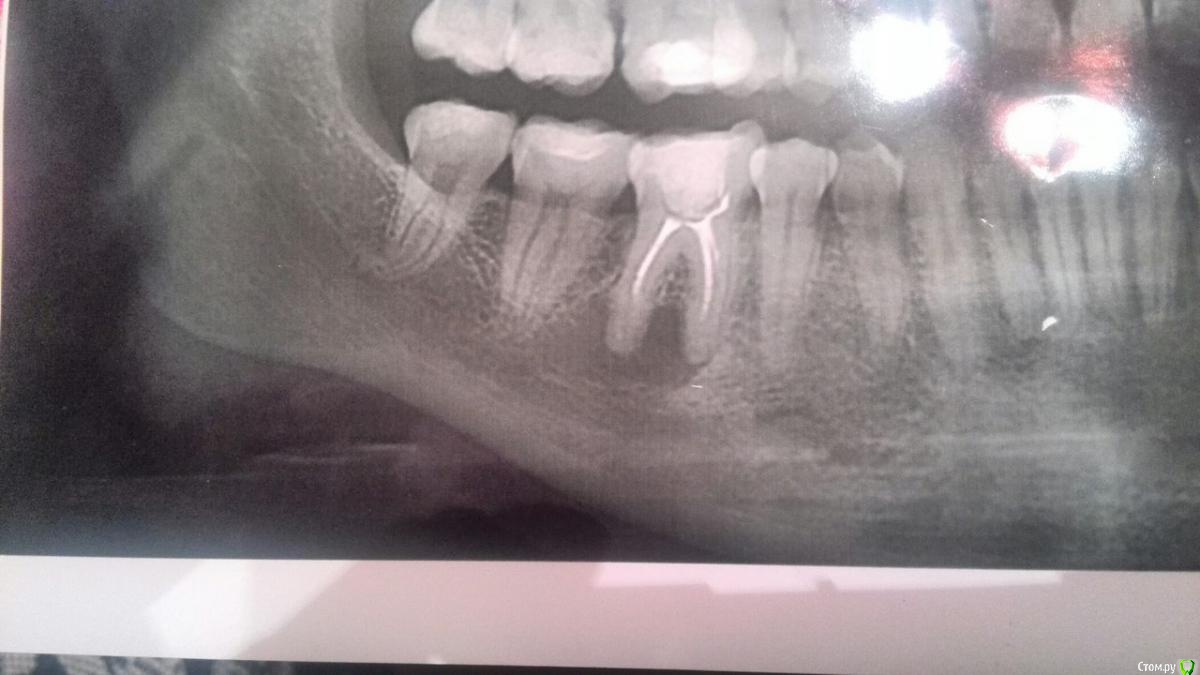

Nikki123 Опубликовано 31 января, 2017 Поделиться Опубликовано 31 января, 2017 (изменено) Добрый день ! Вопрос к врачам-терапевтам - как вы считаете, возможно ли вылечить кисту такого размера ? Двое специалистов меня напугали тем, что киста близко к нижнечелюстному каналу и корню седьмого зуба(то есть можно потерять еще и его), плюс вероятно склерозированы каналы, так как зуб лечился в раннем школьном возрасте и вообще она слишком большая - только удаление и быстрее.. А один дал надежду, сказал, что теоретически возможно - но он хирург. Хотелось бы услышать еще какое-нибудь мнение. Был ли в вашей практике такой опыт ..Спасибо заранее! Изменено 31 января, 2017 пользователем Nikki123 Ссылка на комментарий

red_butler Опубликовано 31 января, 2017 Поделиться Опубликовано 31 января, 2017 Спасибо! Но уже два терапевта отказались от лечения после очной консультации...Причем они найдены были именно по отзывам в плане " вылечили кисту"..На этот форум последняя надежда)мы видим только rg, возможно есть скрытые проблемы. Ссылка на комментарий